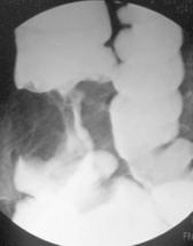

- Endoscopia

- Éscanner